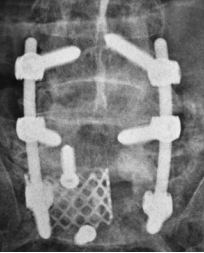

Mr O, an elderly man, was recently admitted for severe low back pain of two months duration. He had chronic low back pain on and off for many years. His pain this time was so severe that he could sit for only a short while. He could barely walk a few meters. The neurological examination was normal. X-ray of his lumbar spine revealed the feature of “’ bamboo spine’ typical of ankylosing spondylosis. There was a fracture through the ossified L5-S1 disc space which was widely opened. Flexion and extension x-ray showed there was considerable instability at the L5-S1 segment. Mr O underwent a two-stage surgery. The 1st stage was posterior L4 to S1 pedicle screw instrumentation. The 2nd stage anterior L5-S1 strut grafting with titanium mesh and fibular allografts was performed 5 days later. Post surgery, Mr O was relieved of his pain and was ambulating.

If a spinal fracture occurs, the bone displacement at the fracture site tends to be severe as all spine motions are concentrated at the fracture site. The excessive motion at the fracture site results in poor fracture healing. Hence the fracture in an ankylosed spine has to be treated with very rigid surgical stabilization. This usually involves two stages anterior and posterior stabilization.